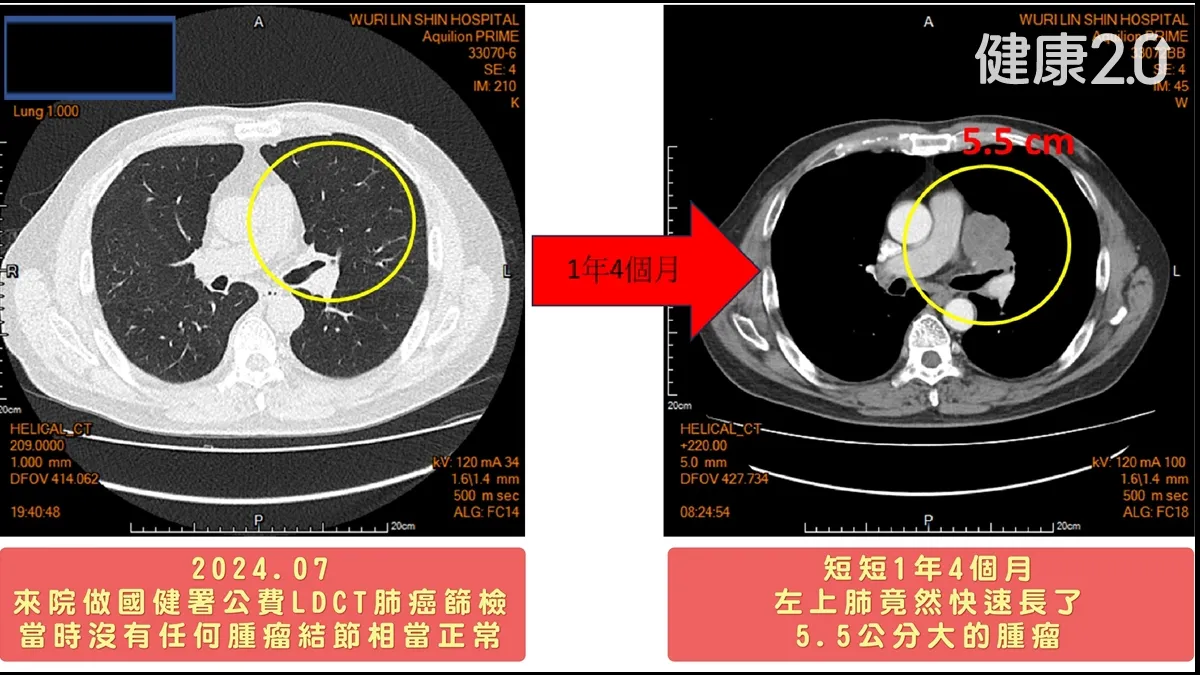

沒有誤診!烏日林新醫院癌症副院長暨胸腔內科許人文醫師分享案例,台中一名63歲黃先生年紀不算大,但菸齡長達40年,符合國健署提供的公費低劑量電腦斷層掃描(LDCT)肺癌篩檢的高危險群身分,1年多前他前往醫院檢查,影像顯示肺癌沒有任何腫瘤結節,相當正常。他以為自己體質好,不但從此高枕無憂,而且繼續每天抽2包菸的習慣,全將醫師給他的戒菸警告拋在腦後。

然而,由於黃男長期抽菸且合併慢性咳嗽與胸悶等症狀,三不五時就會向醫院報到,在接受檢查1年4個月後,他在門診的追蹤檢查時,竟發現1顆5.5公分大的腫瘤,經穿刺切片後病理報告證實為「小細胞肺癌」,進一步的全身正子斷層掃描更清楚看到,癌細胞已轉移至兩側縱膈腔與左側頸部淋巴結,並侵犯到心包膜,且左側惡性肋膜積水,確定癌症期別為第四期末期,是肺癌中預後最差的「癌王」。

歷經生死交關,再度獲得重生的黃先生回憶起得知罹癌的當下,仍不敢置信地說:「1年多前檢查過都沒事,怎麼這麼快變成小細胞肺癌末期?」他說,短短1年4個月他的心情如同洗三溫暖,此後他再也不敢抽菸了!也奉勸還心存僥倖的癮君子及早戒菸、定期檢查,才能遠離肺癌威脅。